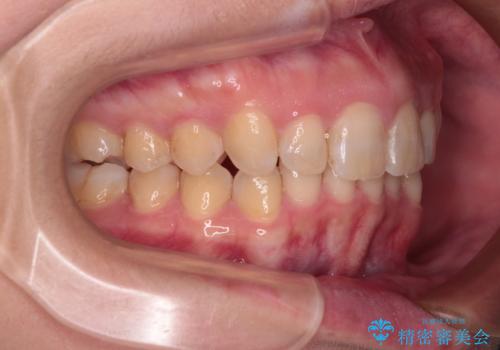

- 上の前歯の出っ歯と前歯の深い咬み合わせを治したいとのことで来院された患者様です。

上顎の歯は後方移動とIPR(歯と歯の間を削る)によって口元が引っ込むように、下顎は歯列全体の拡大とIPRによって上顎とバランスよく咬み合うように設計し、インビザラインにより治療を行うこととしました。

上顎歯列の後方への移動量が多く、右側の奥歯の咬み合わせを改善する必要もあったため、治療には長期間を要しました。